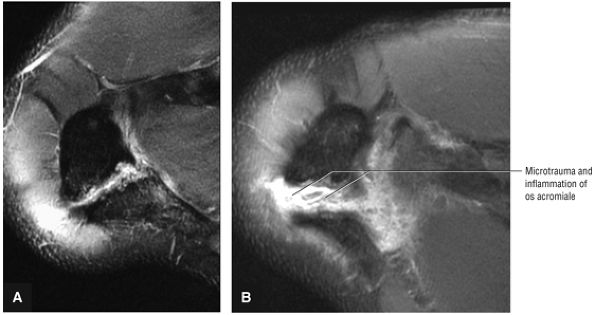

-

Primary extrinsic impingement is associated with abrasion of the rotator cuff against the inferior surface of the acromion.

Subacromial keel spurs are located on the anteroinferior lateral portion of the acromion.